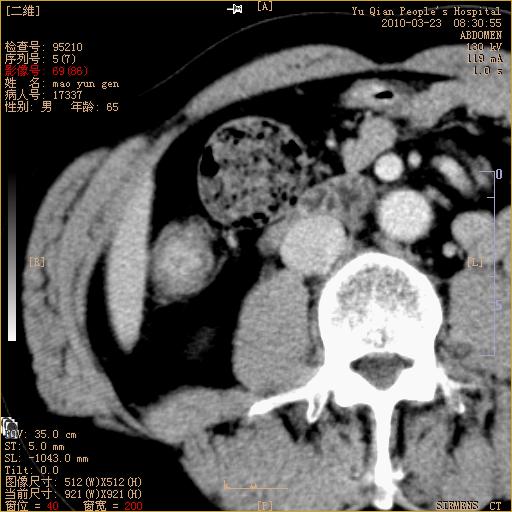

标题: CT25266:消瘦月余,前来肝部检查,请看看肠腔 [打印本页]

标题: CT25266:消瘦月余,前来肝部检查,请看看肠腔

升结肠肠壁增厚,不均强化,考虑升结肠腺癌可能性,建议肠镜检查。

1)考虑升结肠癌。2)右肾小囊肿。